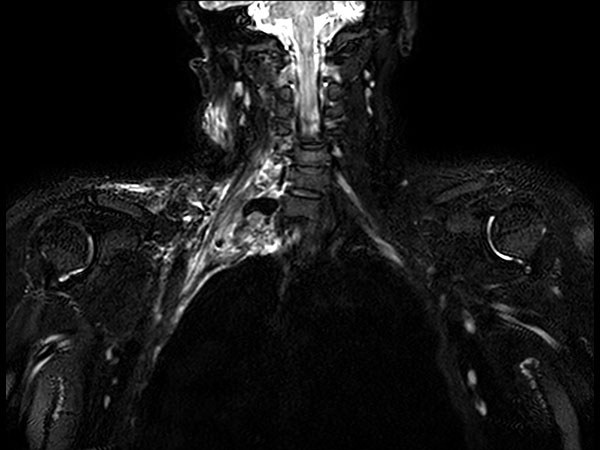

Coronal STIR TSE